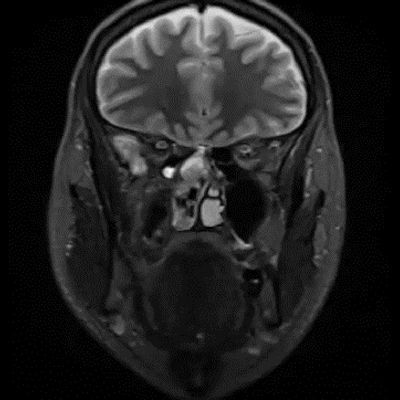

- A) Koronal T2A görntüde sağ süperior nazal kavite içerisinde hafif ekpansil karakterde, keskin sınırlı, nisbeten lobüle konturlu heterojen ara sinyal intensitye sahip yumşak doku lezyonu izleniyor (oklar).